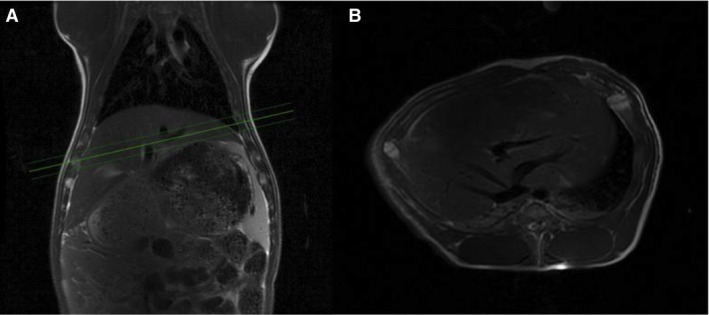

A 3T GE Hdx MR scanner (GE Healthcare, Milwaukee, WI) was used for both MRI and hyperpolarizied MRS. An integrated body coil was used for proton imaging. Respiratory frequencies excitations were gated by the animal's respiratory cycles. Localization was performed with a standard three plane single shot fast spin echo localizer sequence, TR = 2 sec and TE = 98 ms. Subsequently, anatomical fast spin echo images were acquired with axial coronal and oblique 18 slices of 8 mm slice thickness, TR = 5 s and TE = 92 ms (Fig. 2). These images were used for locating the 13C slice selection across the liver in the subsequent DNP measurement. For 13C spectroscopy, the scanner was equipped with a bore‐insertable 13C volume excitation resonator integrated in the patient table (GE Healthcare). This was combined with a 16‐channel flexible receiver heart array coil (Rapid Biomedical, Rimpar, Germany) which consisted of two paddles, each with eight channels for placement underneath and on top of the animal to ensure sufficiently uniform coil sensitivity in the liver slice volume.

Figure 2.

Magnetic resonance (MR) spectra and proton images. MR‐Proton images of one of the pigs, showing a coronal image (A) and oblique image through the liver (B). The three green lines show the 1 cm section for the 13C MRS time series.